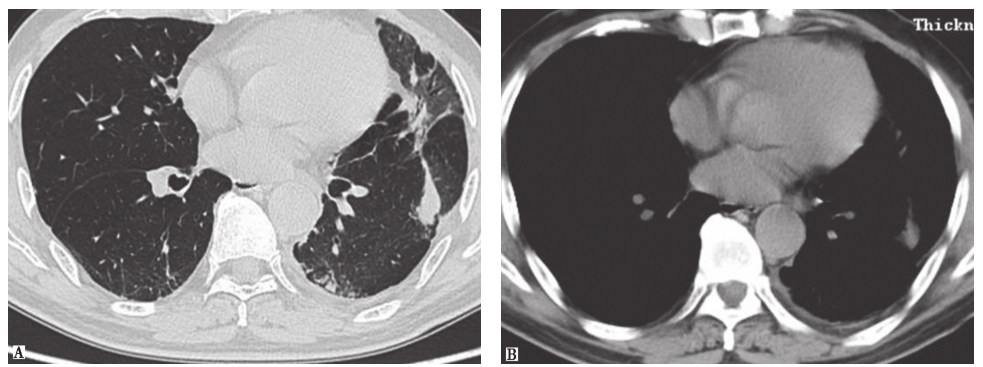

(2)隐源性机化性肺炎(COP):指没有明确致病原(感染)和其他临床伴随疾病(如结缔组织疾病等)情况下出现的以肺泡内、肺泡管、呼吸性细支气管及终末细支气管腔内有机化性肉芽组织为病理特点,对糖皮质激素治疗反应良好的间质性肺疾病。COP亚急性起病,病程多在2个月以内,发病前可出现流感样症状,最常见的临床症状为干咳和不同程度的呼吸困难,查体可在病变肺部位闻及爆裂音。COP的HRCT表现可为肺实变影或不规则线状、条索影沿支气管血管束分布,以及随机分布的磨玻璃影,病变呈游走性(图2)。肺活检病理是COP确诊的金标准。大部分COP对激素治疗反应好,临床症状及影像学可迅速改善,预后良好。

图2隐源性机化性肺炎胸部CT表现

男性患者,66岁,咳嗽、气喘2个月余。胸部CT可见以左肺为主的磨玻璃高密度影伴实变病灶,沿支气管血管束走行分布,并见右下肺胸膜下间隔旁气肿。临床诊断为隐源性机化性肺炎